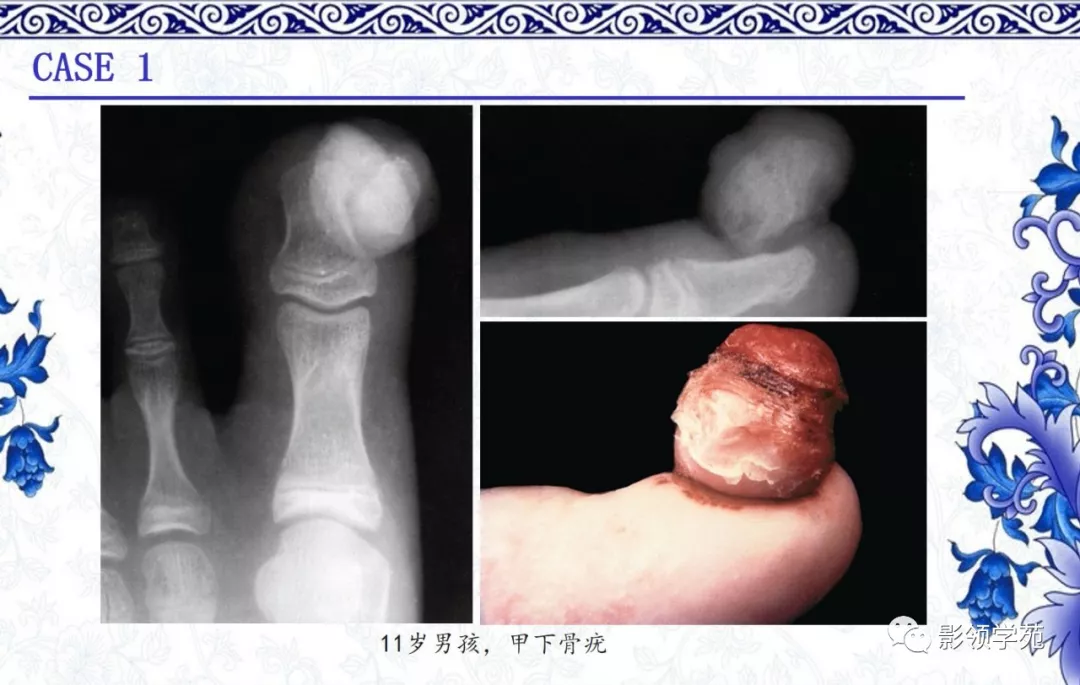

4.甲下外生骨疣